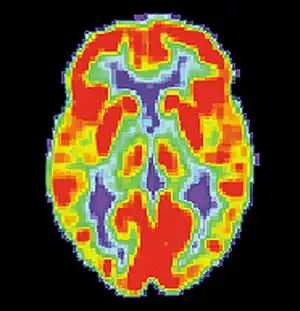

PET scan of a healthy brain - Image courtesy of US National Institute on Aging Alzheimer's Disease Education and Referral Center

PET scan of brain with AD - Image courtesy of US National Institute on Aging Alzheimer's Disease Education and Referral Center